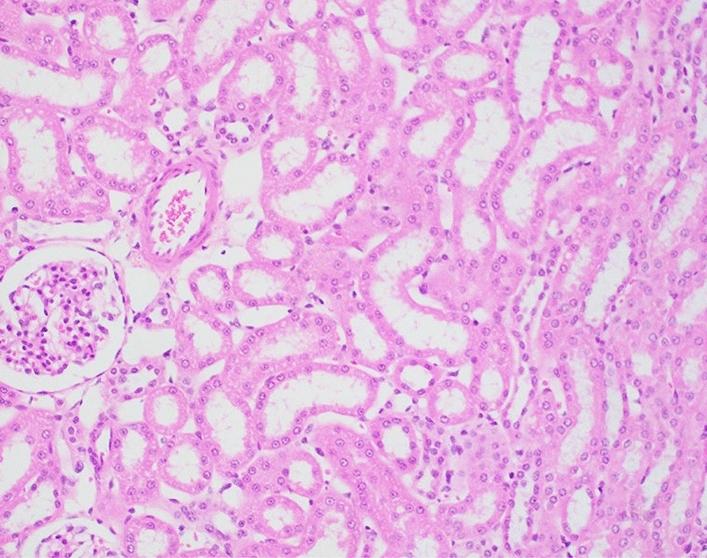

Exposure to high, marginally lethal doses or higher of ionizing radiation, either intentional or accidental, results in injury to various organs. Currently, there is only a limited number of safe and effective radiation countermeasures approved by US Food and Drug Administration for such injuries. These approved agents are effective for only the hematopoietic component of the acute radiation syndrome and must be administered only after the exposure event: currently, there is no FDA-approved agent that can be used prophylactically. The nutraceutical, gamma-tocotrienol (GT3) has been found to be a promising radioprotector of such exposure-related injuries, especially those of a hematopoietic nature, when tested in either rodents or nonhuman primates. We investigated the nature of injuries and the possible protective effects of GT3 within select organ systems/tissues caused by both non-lethal level (4.0 Gy), as well as potentially lethal level (5.8 Gy) of ionizing radiation, delivered as total-body or partial-body exposure. Results indicated that the most severe, dose-dependent injuries occurred within those organ systems with strong self-renewing capacities (e.g., the lymphohematopoietic and gastrointestinal systems), while in other tissues (e.g., liver, kidney, lung) endowed with less self-renewal, the pathologies noted tended to be less pronounced and less dependent on the level of exposure dose or on the applied exposure regimen. The prophylactic use of the test nutraceutical, GT3, appeared to limit the extent of irradiation-associated pathology within blood forming tissues and, to some extent, within the small intestine of the gastrointestinal tract. No distinct, global pattern of bodily protection was noted with the agent's use, although a hint of a possible radioprotective benefit was suggested not only by a lessening of apparent injury within select organ systems, but also by way of noting the lack of early onset of moribundity within select GT3-treated animals.